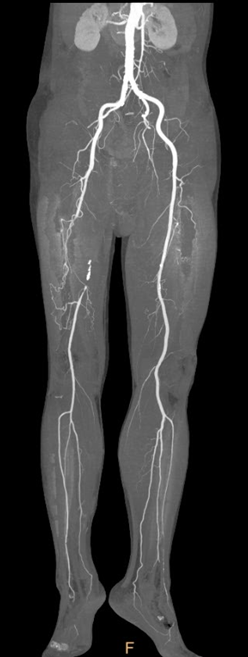

标准化操作流程(Tips)

开通:以内膜下技术为主,逆穿是常用且有效的辅助手段。

预扩:充分预扩张至关重要,需逐级使用高压球囊,最终达到 6mm 直径,以获得足够的管腔。

支架植入:遵循“由远及近”原则,先放置远端 DES,再覆盖中段 VB,最后处理近端。利用 Eluvia 的可调节性优化重叠。

后扩:常规使用 6mm 高压球囊进行后扩张,确保支架充分贴壁和管腔获得。

用药:术中术后必须充分抗凝,推荐“双通道”抗栓方案(如利伐沙班+阿司匹林),以模拟 bypass 的血流动力学效果。